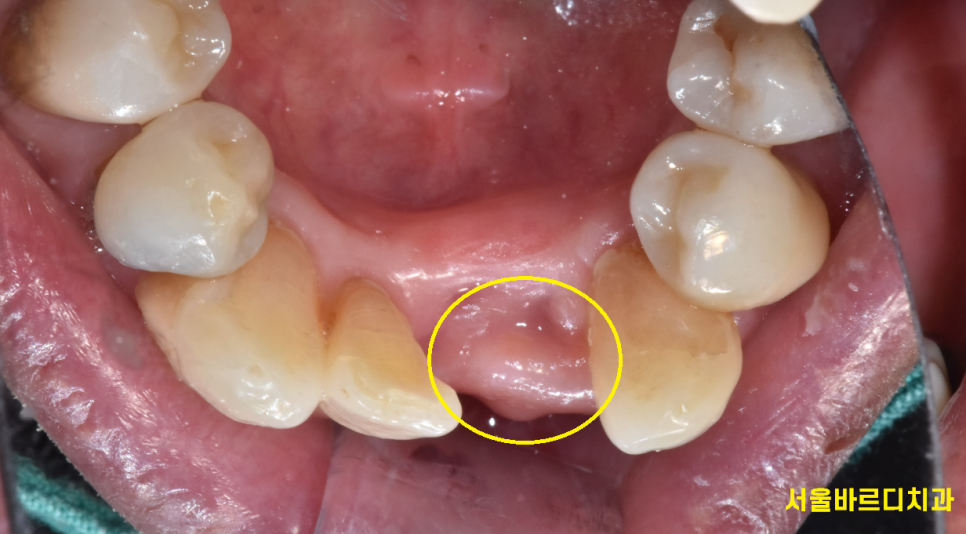

그리고 치아가 상실된지 오래되어

치아가 쓰러져 자리가 부족할 때

임플란트 수술 대안으로 브릿지를 합니다.

위에 환자분도 치아가 빠진지 워낙 오래되어

저 좁은 공간에 치아 3개가 들어가야했습니다.

240408

임플란트는 뼈에 심는건데

공간이 안나오면 브릿지로 대체하죠~